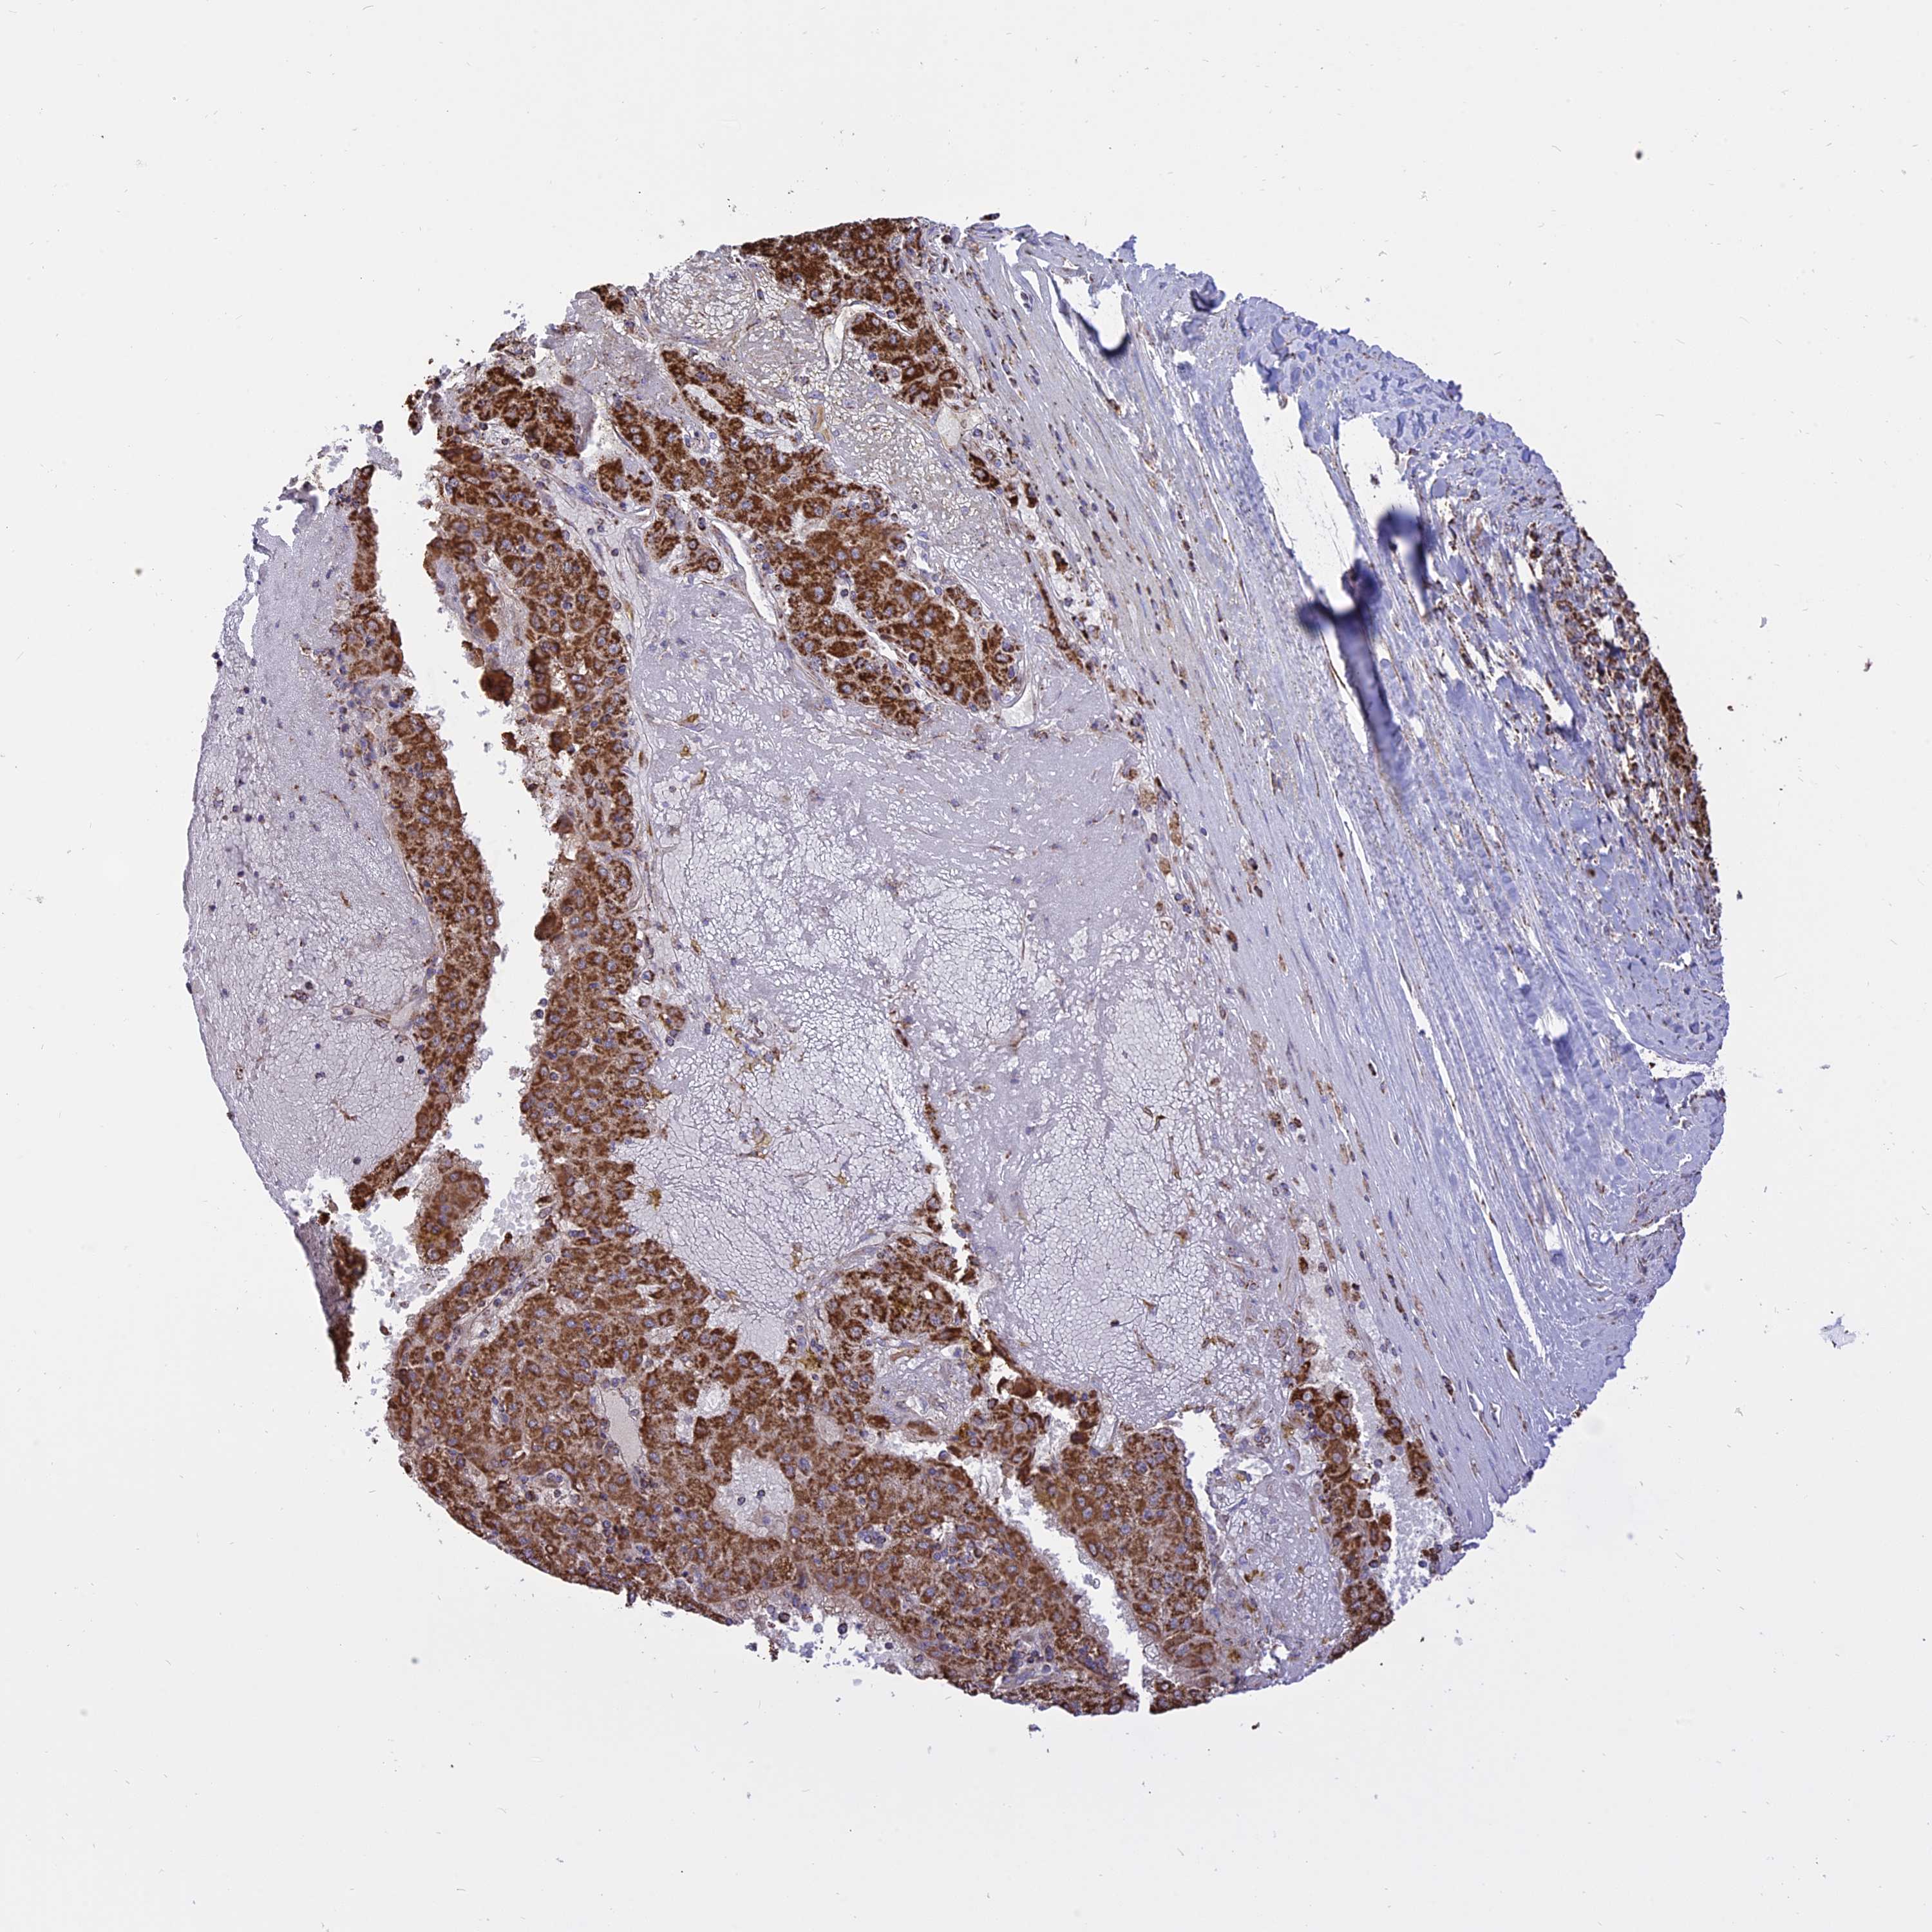

LIVER CANCER - Protein expressioni

A mouse-over function shows sample information and annotation data. Click on an image to view it in a full screen mode. Samples can be filtered based on level of antibody staining by selecting one or several of the following categories: high, medium, low and not detected. The assay and annotation is described here.

Note that samples used for immunohistochemistry by the Human Protein Atlas do not correspond to samples in the TCGA dataset.

Antibody stainingi

Antibody staining in the annotated cell types in the current human tissue is reported as not detected, low, medium, or high, based on conventional immunohistochemistry profiling in selected tissues. This score is based on the combination of the staining intensity and fraction of stained cells.

Each image is clickable and will lead to virtual microscopy that enables deeper exploration of all samples and also displays staining intensity scores, fraction scores and subcellular localization as well as patient and tissue information for each sample.

Antibody HPA041608

Antibody HPA042459

Staining

High

Medium

Low

Not detected

Intensity

Strong

Moderate

Weak

Negative

Quantity

>75%

75%-25%

<25%

None

Location

Nuclear

Cytoplasmic/membranous

Cytoplasmic/membranous,nuclear

Cholangiocarcinoma

Carcinoma, Hepatocellular, NOS